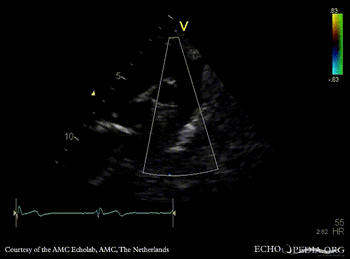

E00727.gif E00728.gif

PSAX: subvalvular membrane PSAX with Color Doppler: high velocity flow in LVOT